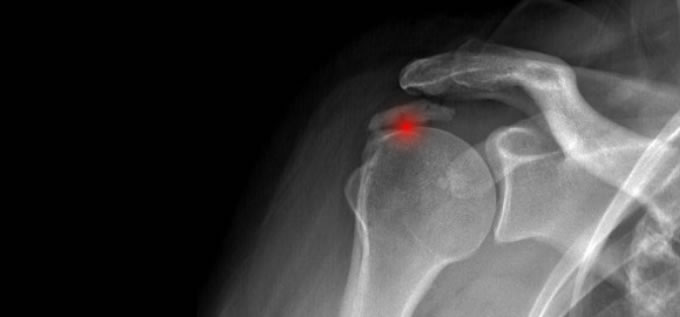

Patología del Manguito Rotador

El manguito rotador o manguito de los rotadores es la confluencia tendinosa de 4 músculos (supraespinoso, infraespinoso, redondo menor y subescapular) que rodean la articulación glenohumeral y que se insertan en la cabeza humeral.

La patología del manguito rotador, es por tanto patología tendinosa, tendinopatía. Va desde la degeneración e inflamación del tendón, a veces con un componente de calcificación, hasta la rotura.

El tendón que se altera con más frecuencia es el del supraespinoso.